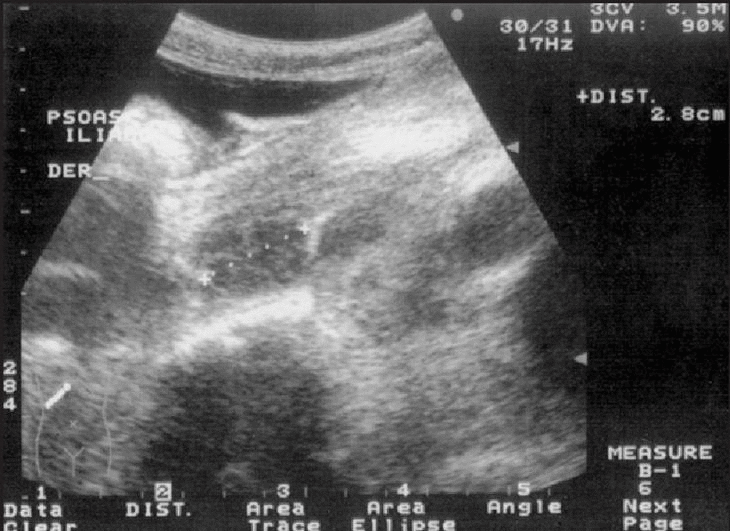

La radiografía de tórax mostró opacidad del seno costofrénico izquierdo. La ecografía abdominal permitió apreciar la existencia de hepatomegalia con leve aumento de la ecogenicidad compatible con esteatosis, fibrosis o granulomatosis; esplenomegalia con múltiples imágenes focales hipoecoicas; vesícula de paredes engrosadas, alitiásica; ascitis abundante, tabicada, y derrame pleural izquierdo. El páncreas y riñones eran normales. En ambas fosas ilíacas se visualizan imágenes hipoecoicas de 145 x 62 x 26 mm a la derecha y 34 x 29 x 22 mm del lado izquierdo compatibles con abscesos del músculo psoas (figs. 1 y 2).

Figura 1. Ecografía abdominal con imagen hipoecoica compatible con absceso del psoas derecho.